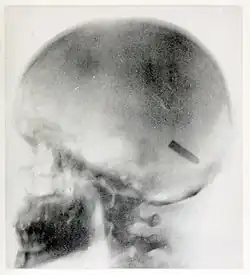

Radiograph by Elizabeth Fleischman of the skull of Private John Gretzer Jr. showing a bullet lodged in the brain.

On August 20, 1899, she took one of her most famous radiographs, an image showing a Mauser 7 mm bullet lodged in the brain of John Gretzer Jr., in the region of the left occipital lobe.[12][15] Private Gretzer, of the 1st Nebraska Volunteers, wounded at Mariboa, Philippines on 27 March 1899 during the Spanish–American War. The private later returned to duty as a mail clerk.[16] Accounts of the case were reported in the 1902 edition of The International Text-Book of Surgery and in newspapers.[17] Another case of a bullet lodged in a soldier's skull, X-rayed by Fleischman was also reported in newspapers in 1899.[18]